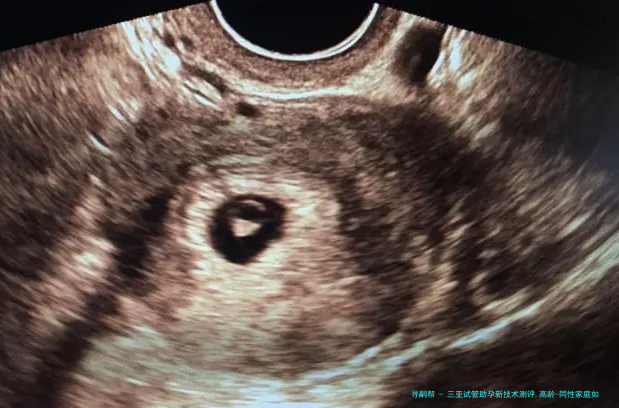

胚胎植入前基因学检查(PGD/PGS)已成为三亚主要潮流机构的标配,新一代测序技术将染色体异样检出率提升至99%以上,大幅减少高龄夫妻因卵子老化导致的早产风险。更前端的试探集结在CRISPR基因编辑,可修复地中海贫血、脊髓性肌肉萎缩症等单基因突变,虽暂处临床研究阶段,但为遗传性疾病家庭提供了新可能。

胚宝宝动作态监测:Time-lapse系统通过每小时捉拿超十万帧影像,结合AI算法分析胚胎分裂速度、细胞对称性等200+参数,较守旧样子学评估将优质胚胎检查筛选准确程度提高30%-40%

玻璃化冷冻技术使胚胎复苏存活率达百分之九十八,卵子保存复苏率进展百分之九十一。针对卵巢功能衰落者,线粒体体替换技术通过替换衰老细胞器,使42岁以上女性活产率从百分之十五跃升至28.7%

三十八岁以上女性卵子非整倍体率超60%,需首先选择备有PGT-A(非整倍体筛查) 技术的机构,结合AI预测模型筛查染色体正常胚胎,将四十二岁临床妊娠率从12%提至39%。反复移植失败者,可以借助无创胚胎基因诊断(niPGT) 通过培育液游离DNA筛查,防止活检伤害胚胎,活产率提升至75%